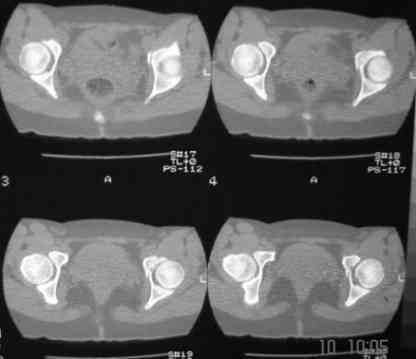

В больнице вправили вывих бедра, три недели на вытяжении. Беспокоят боли в левом тазобедренном суставе и левом крестцово-подвздошном сочленении. Ходит с тростью. Снимок - в приложении. Направил на КТ, заключение: разрыв симфиза и левого крестцово-подвздошного сочленения, переломы крыши и заднего края вертлужной впадины, горизонтальной ветви лонной кости слева.

Уважаемый д-р Булахтин, на мой взгляд единственное повреждение требующее синтеза - застарелый разрыв лона. Низкий перелом передней колонны безопасен, повреждения свода не вижу, неясно что было сзади (скорее боковая масса)лучше сделать обзорный снимок прямой и Inlet.

Очень похоже на повреждение от бокового сжатия.

Признаков разрыва сочленения не вижу, м.б. контрлатеральный перелом боковой массы.

Если был задний вывих, то повреждение должно локализоваться сзади. В данном случае перелом спереди, как результат сдавления лонного сочленения.